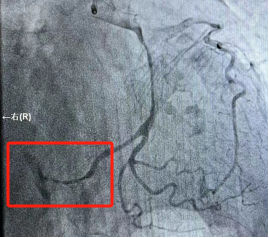

回旋支未见明显狭窄,远端可见慢血流